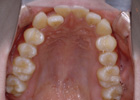

歯を抜かずに治療ができた例

治療前

治療後